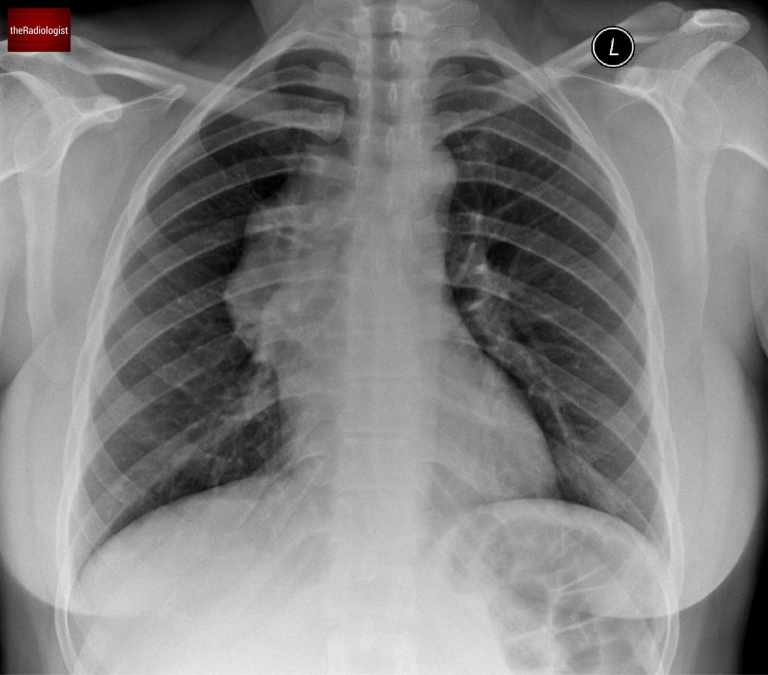

A female in her 30s presents with chest pain and has a chest X-Ray through her GP. Can you see anything that might help you localise the abnormality?

PA view of a chest X-Ray of a female in her 30s

Follow up for lymphoma usually involves a PET-CT however have a look at the post chemotherapy X-Ray. This shows that the mass has completely resolved.

The follow -up chest X-Ray after chemotherapy shows resolution of the anterior mediastinal mass and now a normal contour on the right side of the mediastinum.